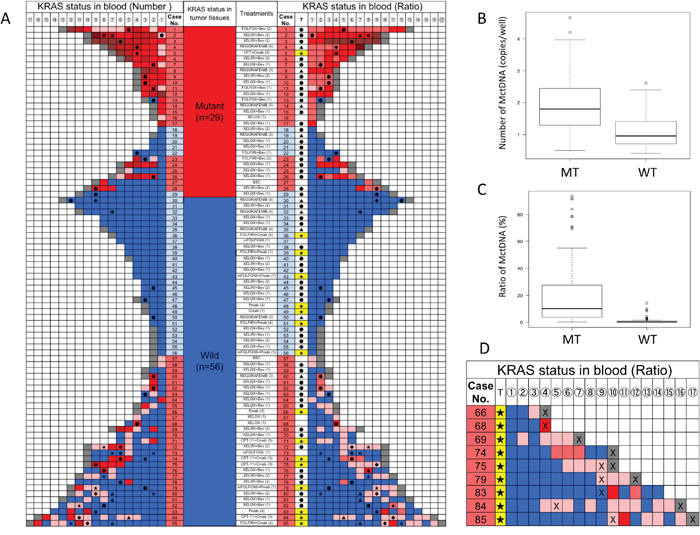

A KRAS monitoring image from mCRC patients treated with various drugs during the treatment lines is shown in Figure 1A. KRAS assessment in tumor tissues identified 29 patients with the mutant-type (MT) and 56 patients with the wild-type (WT). Assessment of KRAS status in blood incorporated both the number of MctDNA and the ratio of MctDNA.

Figure 1: KRAS monitoring of mCRC patients and comparison of MctDNA between MT and WT (A) KRAS monitoring of mCRC patients treated with various drugs across several treatment lines. Initial assessments for circulating tumor DNA with KRAS mutations (MctDNA) varied by treatment line and regimen and are shown under “treatment (lines)”; (XELOX (1) means that XELOX was given as the first-line treatment). KRAS status in tumor tissues is shown. Patients with mutations (red), those without (blue). KRAS assessment in tumor tissues are under “KRAS status in tumor tissues” with red for patients with the mutant-type (MT) and blue for patients with the wild-type (WT). Monitoring MctDNA is shown under “KRAS status in blood”, ordered by timing of blood examination (①→⑯). MctDNA was assessed using two methods for “KRAS status in blood”. Left column under “KRAS status in blood (number)” indicates the number of MctDNA. MctDNA not detected (blue); detection of MctDNA in fewer than 10 copies/well (pink); 10 ≤ MctDNA < 50 copies/well (light red); 50 ≤ MctDNA < 100 copies/well (red); 100 ≤ MctDNA < 100 copies/well (light brown); MctDNA ≥ 1000 copies/well (brown); end of treatment because of disease progression (gray). Right column under “KRAS status in blood (ratio)” shows ratio of MctDNA among total circulating cell-free DNA (MctDNA and circulating cell-free DNA without KRAS mutations). The mutation ratio was calculated by fractional abundance (MctDNA/ total circulating cell-free DNA). MctDNA not detected (blue); detection of MctDNA less than 1% (pink). MctDNA ≤ 1 < 10% (light red); 10 ≤ MctDNA < 30% (red); 30 ≤ MctDNA < 50% (light brown); MctDNA ≤ 100% (brown); end of treatment because of disease progression (gray). ●: anti-VEGF antibody; ▲: regorafenib; ★: anti-EGFR antibody; ◆: TAS-102. (B) Comparison of number of MctDNA between patients with MT and WT in tumor tissues. Vertical axis represents logarithm. (C) Comparison of ratio of MctDNA between patients with MT and WT in tumor tissues. The mutation ratio was calculated by fractional abundance (MctDNA / total circulating cell-free DNA). Vertical axis represents mutation ratio × 102. (D) Initial detection of MctDNA in patients with WT treated with anti-EGFR antibody. T: treatment; ★: anti-EGFR antibody; X: detection of radiological disease progression. Detection of MctDNA less than 1% (pink); MctDNA ≤ 1 < 10% (light red); 10 ≤ MctDNA < 30% (red).

In 29 patients with the MT, MctDNA was detected in 23 patients (79.3%) (Figure 1A). Among 18 patients who underwent second-line or subsequent treatment lines, MctDNA was detected in 17 patients (94.4%). Details of the clinical course of these 29 patients is shown in Table 1. The median value of MctDNA was 64.0 copies/well (3.2–45800) for the number and 10.10% (0.26–93.60) for the ratio in these 29 patients (Figure 1B and 1C). Comparing progression-free survival (PFS) of the first-line treatment between patients with MctDNA and without, there was a significant difference in PFS (Figure 2A), with a worse outcome in patients with MctDNA (22.0 vs 3.0 months, p = 0.0007). Most patients showed a continuous change with increasing MctDNA (Figure 3A and 3C). Four patients had a stable MctDNA level, suggesting a long stable disease (Figures 3B and 4A), and two patients showed a quick decrease in MctDNA with shrinkage of tumors in response to treatment (Figure 3D and Figure 4G).

Dynamics of mutated circulating tumor DNA and outcome in patients with the wild-type

In 56 patients with the WT, MctDNA was detected in 28 patients (50.0%) (Figure 1A). Details of the clinical course of these 56 patients is shown in Table 2. MctDNA was detected in patients treated with anti-EGFR antibody as well as those treated with other drugs such as anti-vascular endothelial growth factor (VEGF) antibody, regorafenib, and TAS-102. Cytotoxic agents without targeted therapies also showed the emergence of MctDNA (Table 3). The median value of MctDNA was 9.1 (2.6–414) for the number and 0.22% (0.002–14.2) for the ratio (Figure 1B and 1C). The median value of MctDNA for the number detected in patients with the WT was 1/7 of that in patients with the MT, suggesting that about 1/7 of tumor cells (14.7%) in patients with the WT might have the KRAS mutation. Comparing first-line treatment between patients with MctDNA and those without, there was a significant difference in PFS (Figure 2B), showing a worse outcome in patients with MctDNA (18.0 vs 7.0 months, p = 0.0017). Most patients showed intermittent changes in elevation; with low levels of MctDNA generally (Figure 3E and 3F), four patients showed a continuous change with an increase (Figure 3G), and five patients showed a transient change with a spike in elevation (quick elevation and disappearance) (Figure 3H), with close to 10 times the amount of MctDNA as the intermittent change in elevation (Figure 3F). Initial detection of MctDNA in WT patients treated with anti-EGFR antibody was likely prior to radiological disease progression (Figure 1D).

MctDNA number and ratio were compared between MT and WT patients. Median values for MT patients were 64.0 copies/well for the number and 10.10% for the ratio, and were 9.1 copies/well for the number and 0.22% for the ratio for WT patients (Figure 1B and 1C). WT patients showed 1/7 the level of MctDNA compared with MT patients (64.0 vs. 9.1), suggesting that WT patients had KRAS mutant cells in 1/7 (14.7%) of tumors. Some smaller pieces of these mutant cells may reach the blood, resulted in the low ratio of KRAS mutant cells (0.22%) in blood of WT patients. The lowest ratio (0.002%) among total cell-free DNA was detected using ddPCR in this analysis. WT patients showed fluctuating changes in the ratio of MctDNA, at around 0.01% of the detection sensitivity of ddPCR, which may have resulted in intermittent detection of MctDNA in WT patients. In contrast, MT patients showed a high ratio of MctDNA (10.10% (0.26–93.60)), allowing for the continuous detection of MctDNA. The lowest ratio (0.26%) was well within the detection range for ddPCR, with a detection sensitivity of 0.01%.